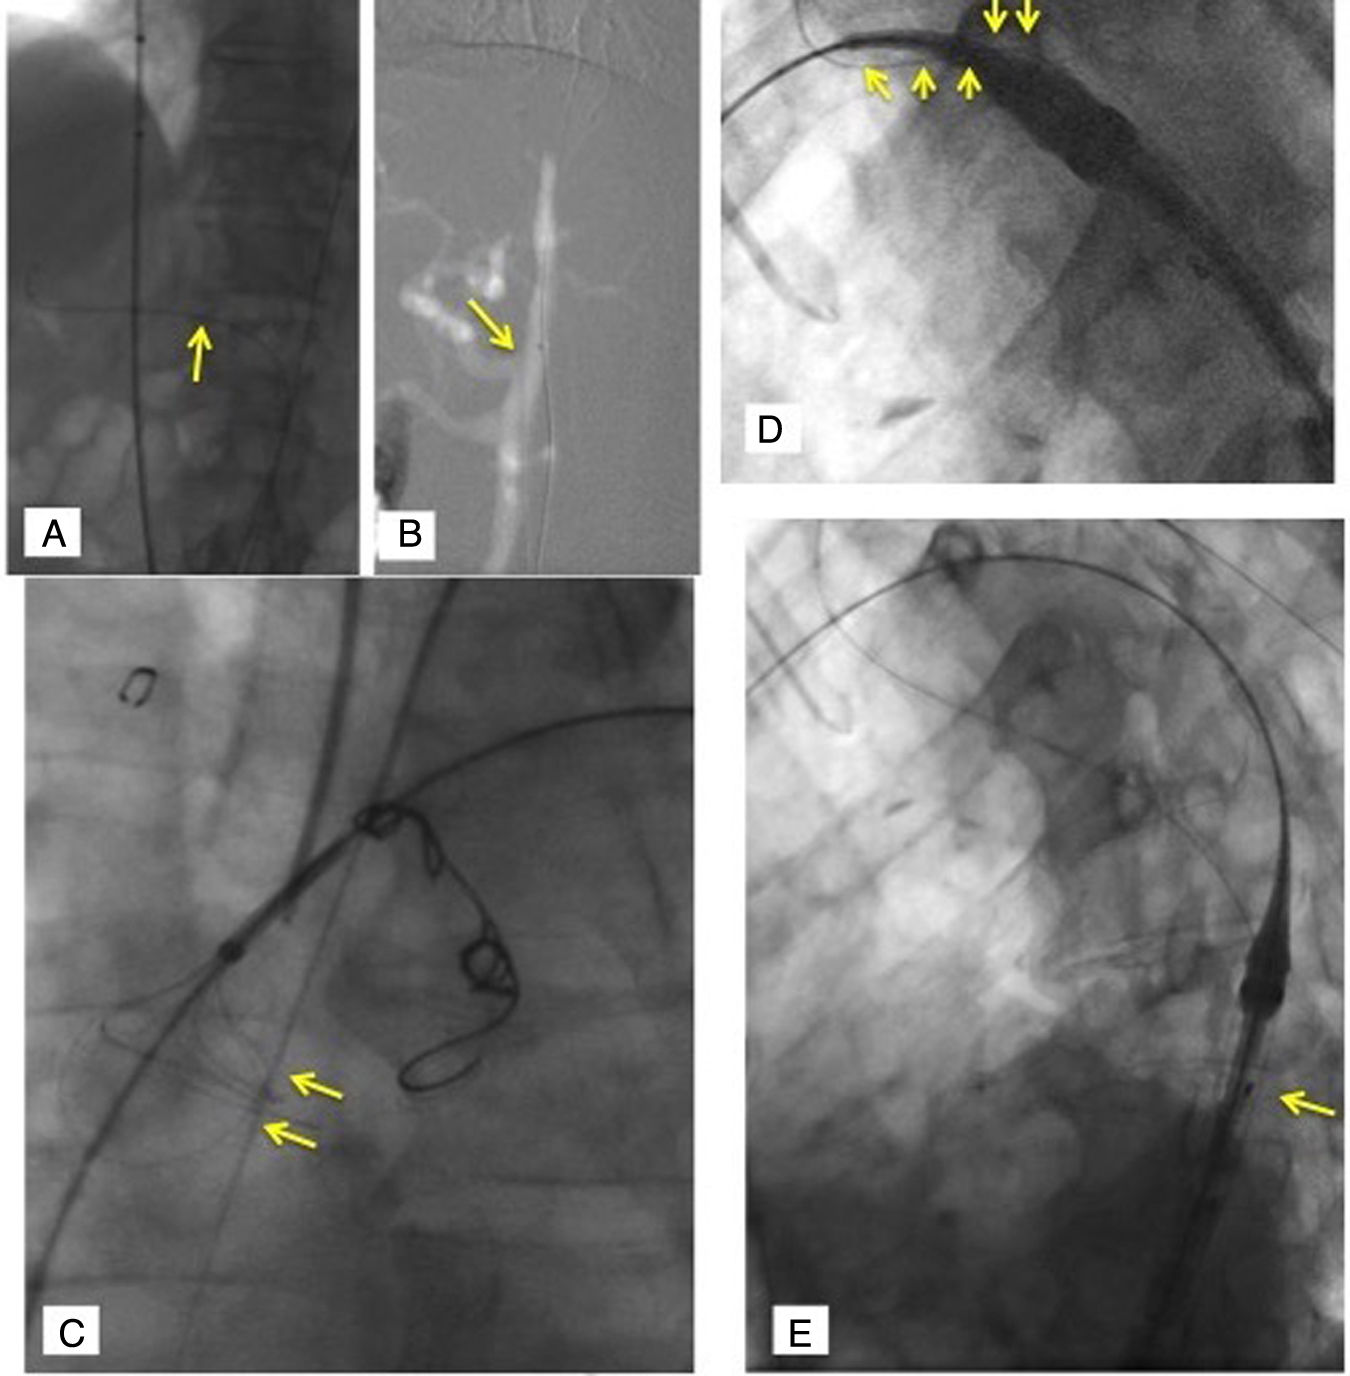

Tras comprobar que la posición de la guía de tracción de ASI y posición de rama ASI es correcta, se retira el introductor externo en un movimiento lento y otro más rápido (mango azul con flecha direccional) (fig. 3).

Figura 3.Implante dispositivo Cratos™ (II): A) CratosTM normoposicionada para iniciar el pull-back del introductor externo (flecha larga), que se realiza en proximidad de ASI (flecha corta), a diferencia de CastorTM. B) CratosTM normoposicionada para iniciar el pull-back del introductor externo (flecha larga), que se realiza en proximidad de ASI (flecha corta), con apoyo de Fusión marcando ostium ASI (flecha larga). C) Retirada de parte floppy de guía Lunderquist® 300mm (COOK, Bloomington, IN, EE. UU.) hacia la nariz (flecha larga) favorece el posicionamiento del catéter liberador en curvatura menor (flechas cortas), permitiendo activar el control del pico de pájaro. D) Con la activación del dial número 4, se retira la nariz / catéter liberador hacia el introductor externo. E) Angiografía control con posicionamiento óptimo de radiomarcadores (en este caso, plataforma de liberación CastorTM): «8» curvatura menor (flecha larga), círculos base de la rama ASI (flecha mediana), círculos extremo distal cubierto de rama ASI (flecha corta). ASI: arteria subclavia izquierda.